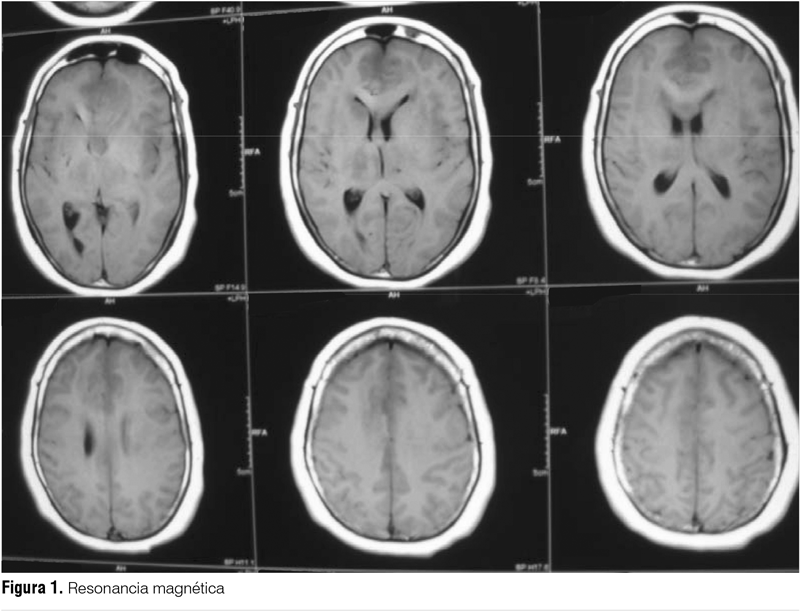

RM de cráneo con perfusión y espectroscopía informa extensa área infiltrativa a nivel de la sustancia blanca fronto-temporal derecha que cruza la línea media a nivel del cuerpo calloso e infiltra el lóbulo frontal izquierdo (figuras 2 y 3). Se afectan ambos tálamos con extensión al pedúnculo cerebral izquierdo hasta protuberancia y otra zona a nivel del carrefour témporo-parieto-occipital izquierdo. Secuencia de perfusión: realce de contraste heterogéneo a nivel frontal parasagital izquierdo. Secuencias de espectroscopía: zonas con disminución del N-acetil aspartato con pico de lípidos-lactatos. Estas características orientan a lesión tumoral primaria del SNC, probable gliomatosis cerebri. Biopsia esterotáxica informa proliferación tumoral maligna primitiva del SNC de estirpe glial de la serie astrocitaria, con moderada anisocariosis y anisocitosis compatible con gliomatosis cerebri. Presenta mala evolución clínica con depresión de conciencia, no iniciándose tratamiento oncoespecífico, se realizan medidas de confort. Fallece a los dos meses del diagnóstico.

La RM con espectroscopía es usada recientemente para evaluar si estamos ante una enfermedad estable o progresiva, mostrando un incremento de los niveles de glicina/inositol, siendo de utilidad como factor pronóstico(3,9).